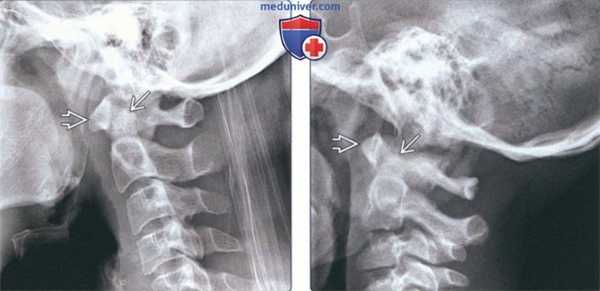

(Слева) На рентгенограмме шейного отдела позвоночника в боковой проекции определяется врожденная гипоплазия зубовидного отростка без нарушения соотношения С1/С2. Передняя дуга С1 слегка увеличена, скорее всею, за счет компенсаторной гипертрофии. Другие аномалии шейного отдела позвоночника отсутствуют.

(Справа) На рентгенограмме шейного отдела позвоночника в боковой проекции определяется легкая гипоплазия зубовидного отростка с компенсаторным увеличением передней дуги С1. Соотношения в краниовертебральном переходе не изменены, другие аномалии отсутствуют.